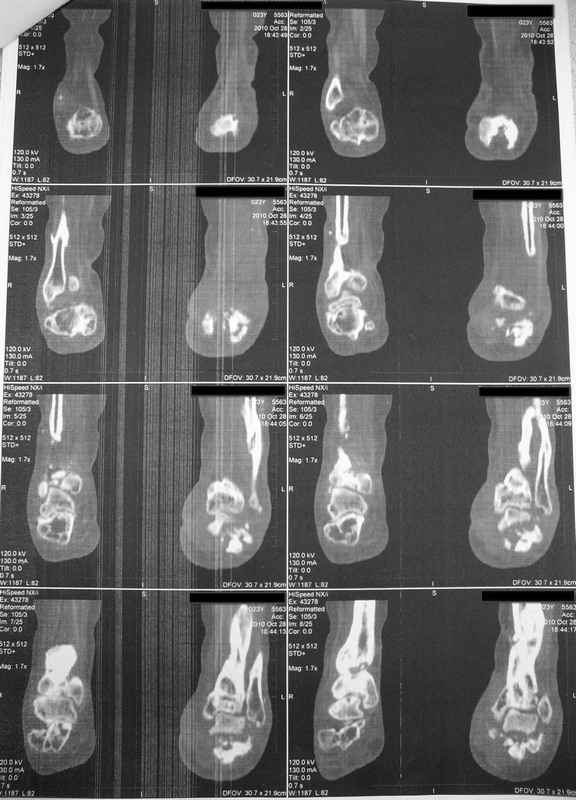

Молодая девушка со сросшимися многооскольчатыми переломами пяток и голеней.Young girl with fractures of the calcaneus Больная Н., 25 лет, падение с высоты (2008 г.). Жалобы на боли в области голеностопных суставах, в области пяток при ходьбе. Лечилась в аппаратах внешней фиксации по поводу открытых оскольчатых переломов обеих голеней, переломов пяток. Далее по поводу несросшихся переломов голеней –ЧКОС аппаратами внешней фиксации. Переломы срослись, аппараты демонтированы весной 2010г. В левой пяточной области в месте проведения спицы имеется сукровичное отделяемое. При ревизии гноя нет. Чем помочь девушке?

Patient N., age 25, falls from heights (2008). Complaints of pain in the ankles, in the heel when walking. She was treated by external fixation on open comminuted fractures of both legs, fractures of the calcaneus. Then she was treated by external fixation from nonunion of both legs. Now fractures are fused, apparatuses removed in the spring of 2010. How to help a girl?